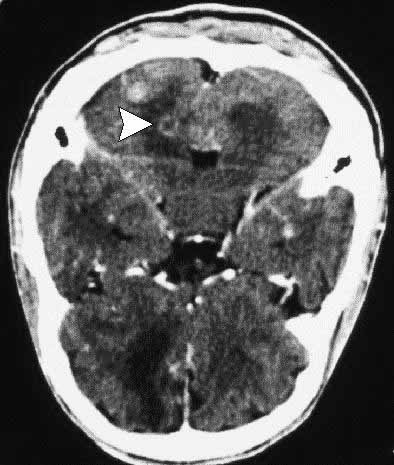

Figura 2. TAC craneal. Lesión focal con realce periférico (flecha).